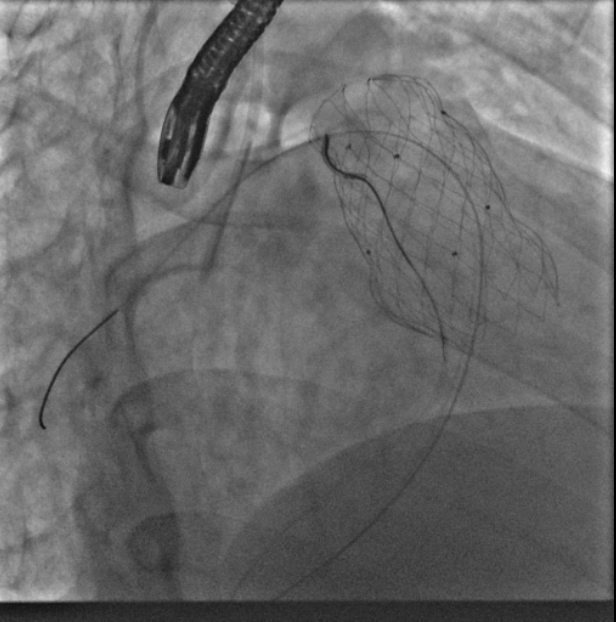

术中测量患者基础主动脉、肺动脉、右心室压力分别为111/58mmHg、31/4/13mmHg、34/1/6mmHg,通过肺动脉造影,术中测量球囊内径为32mm(见图二),选择36-25mm VENUS-P肺动脉瓣膜,在肺动脉造影指引下逐步打开瓣膜。考虑到患者肺动脉分叉较短,存在瓣膜释放后移位风险,故选择高位释放法(图三)。但释放瓣膜后造影提示右肺动脉开口局部被阻挡(图四),复测患者主肺动脉、左肺动脉、右肺动脉压力分别为57/13/25mmHg、55/12/24mmHg、27/7/14mmHg。

图二:术中扩张球囊刚好堵住右室流出道,测量球囊内经为32mm

图三:考虑到患者肺动脉分叉较短,选择高位释放法